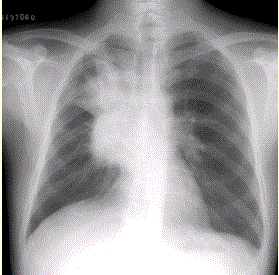

问题 患者男,62岁,痰中带血丝2周,无发热,伴刺激性咳嗽。X线胸片如下图。应诊断为

选项 A.右上肺结核并肺门淋巴结增大 B.肺动脉高压 C.右肺中心型肺癌 D.右肺脓肿 E.升主动脉瘤

答案 C